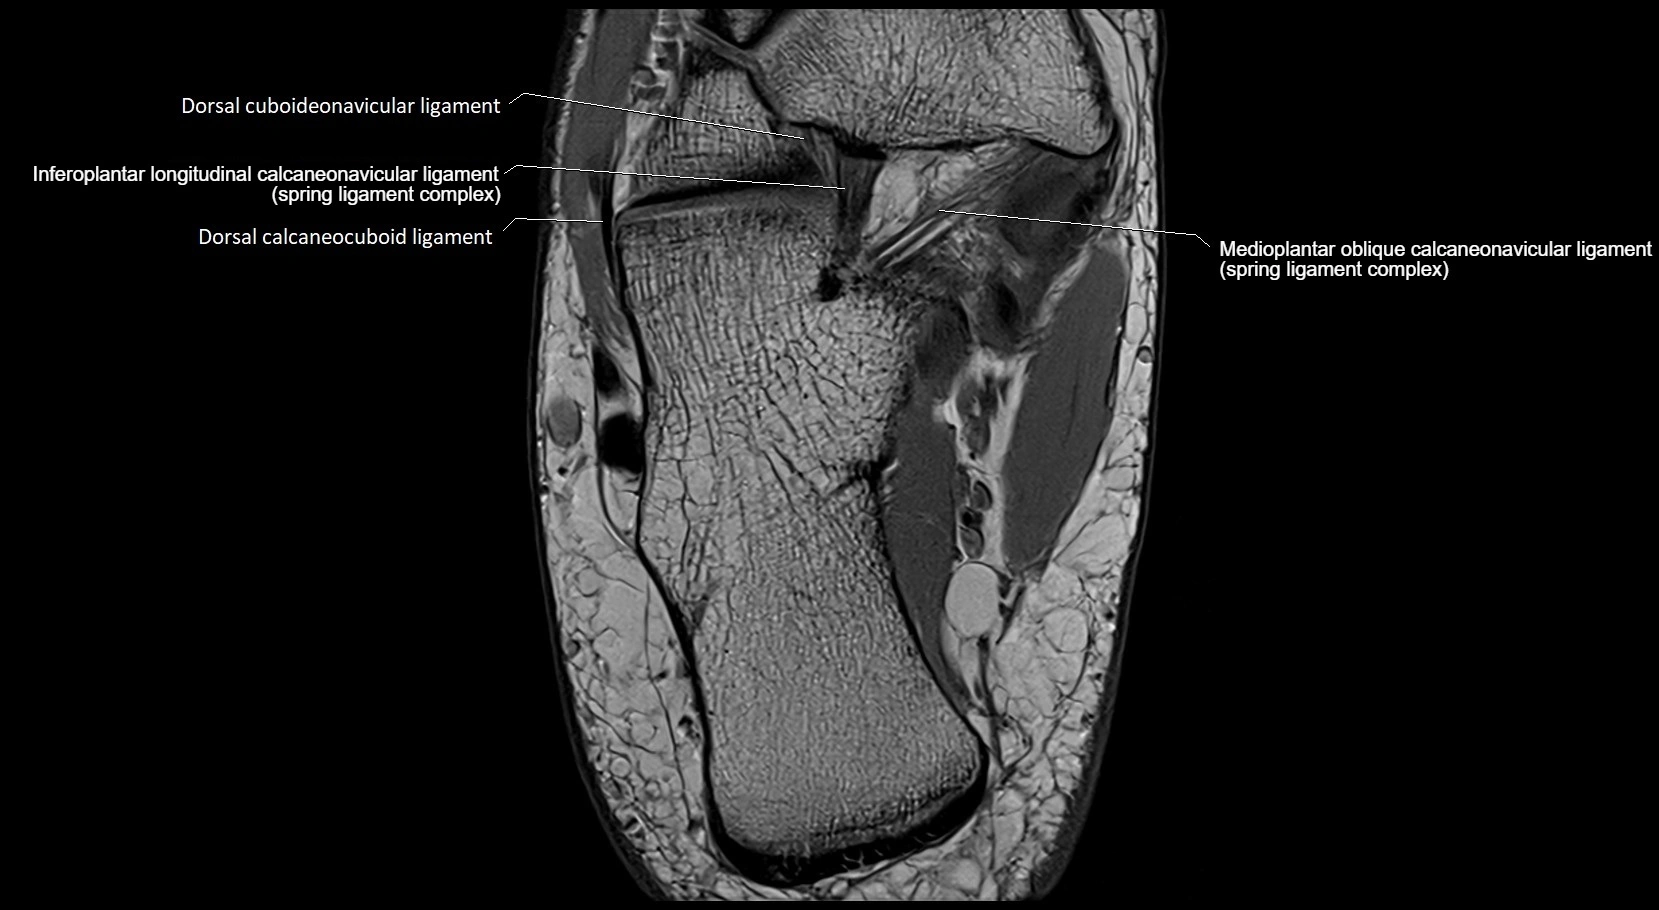

MRI image

image